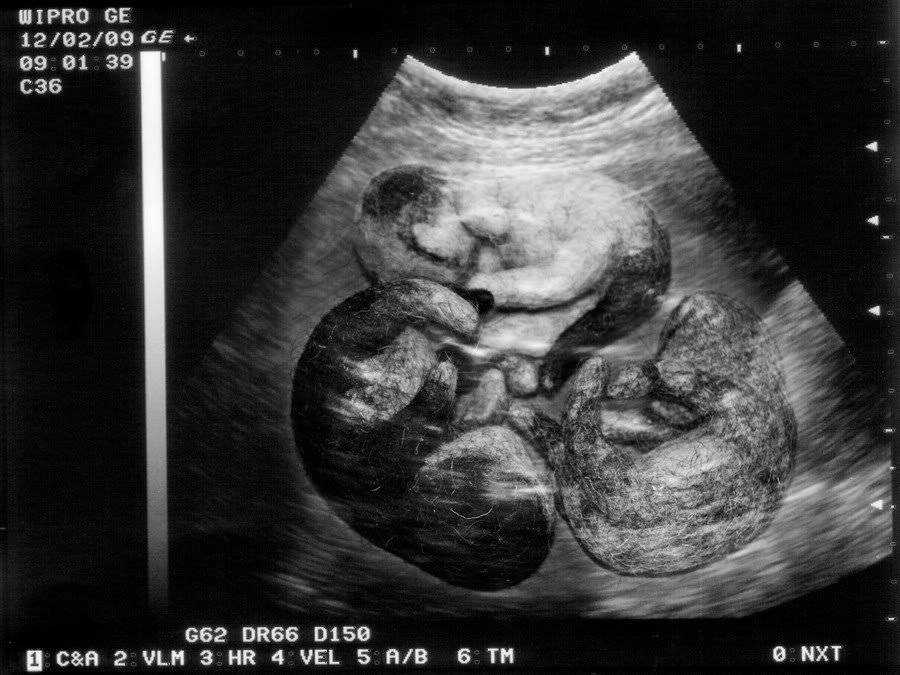

- Научный метод считается самым точным из всех существующих и проводится за неделю-две до предстоящих родов на ультразвуковом оборудовании.

Наиболее точный метод определения количества котят – УЗИ

- Научный . Фелинологи рекомендуют проверить будущую роженицу с помощью УЗИ за неделю до предполагаемых родов. Таким образом, будет точно известно какого приплода ожидать. Ни в коем случае нельзя прощупывать живот кошки руками, чтобы узнать, сколько котят она родит. Пальпация может повредить эмбрионы, привести к психологическому стрессу будущей мамы.